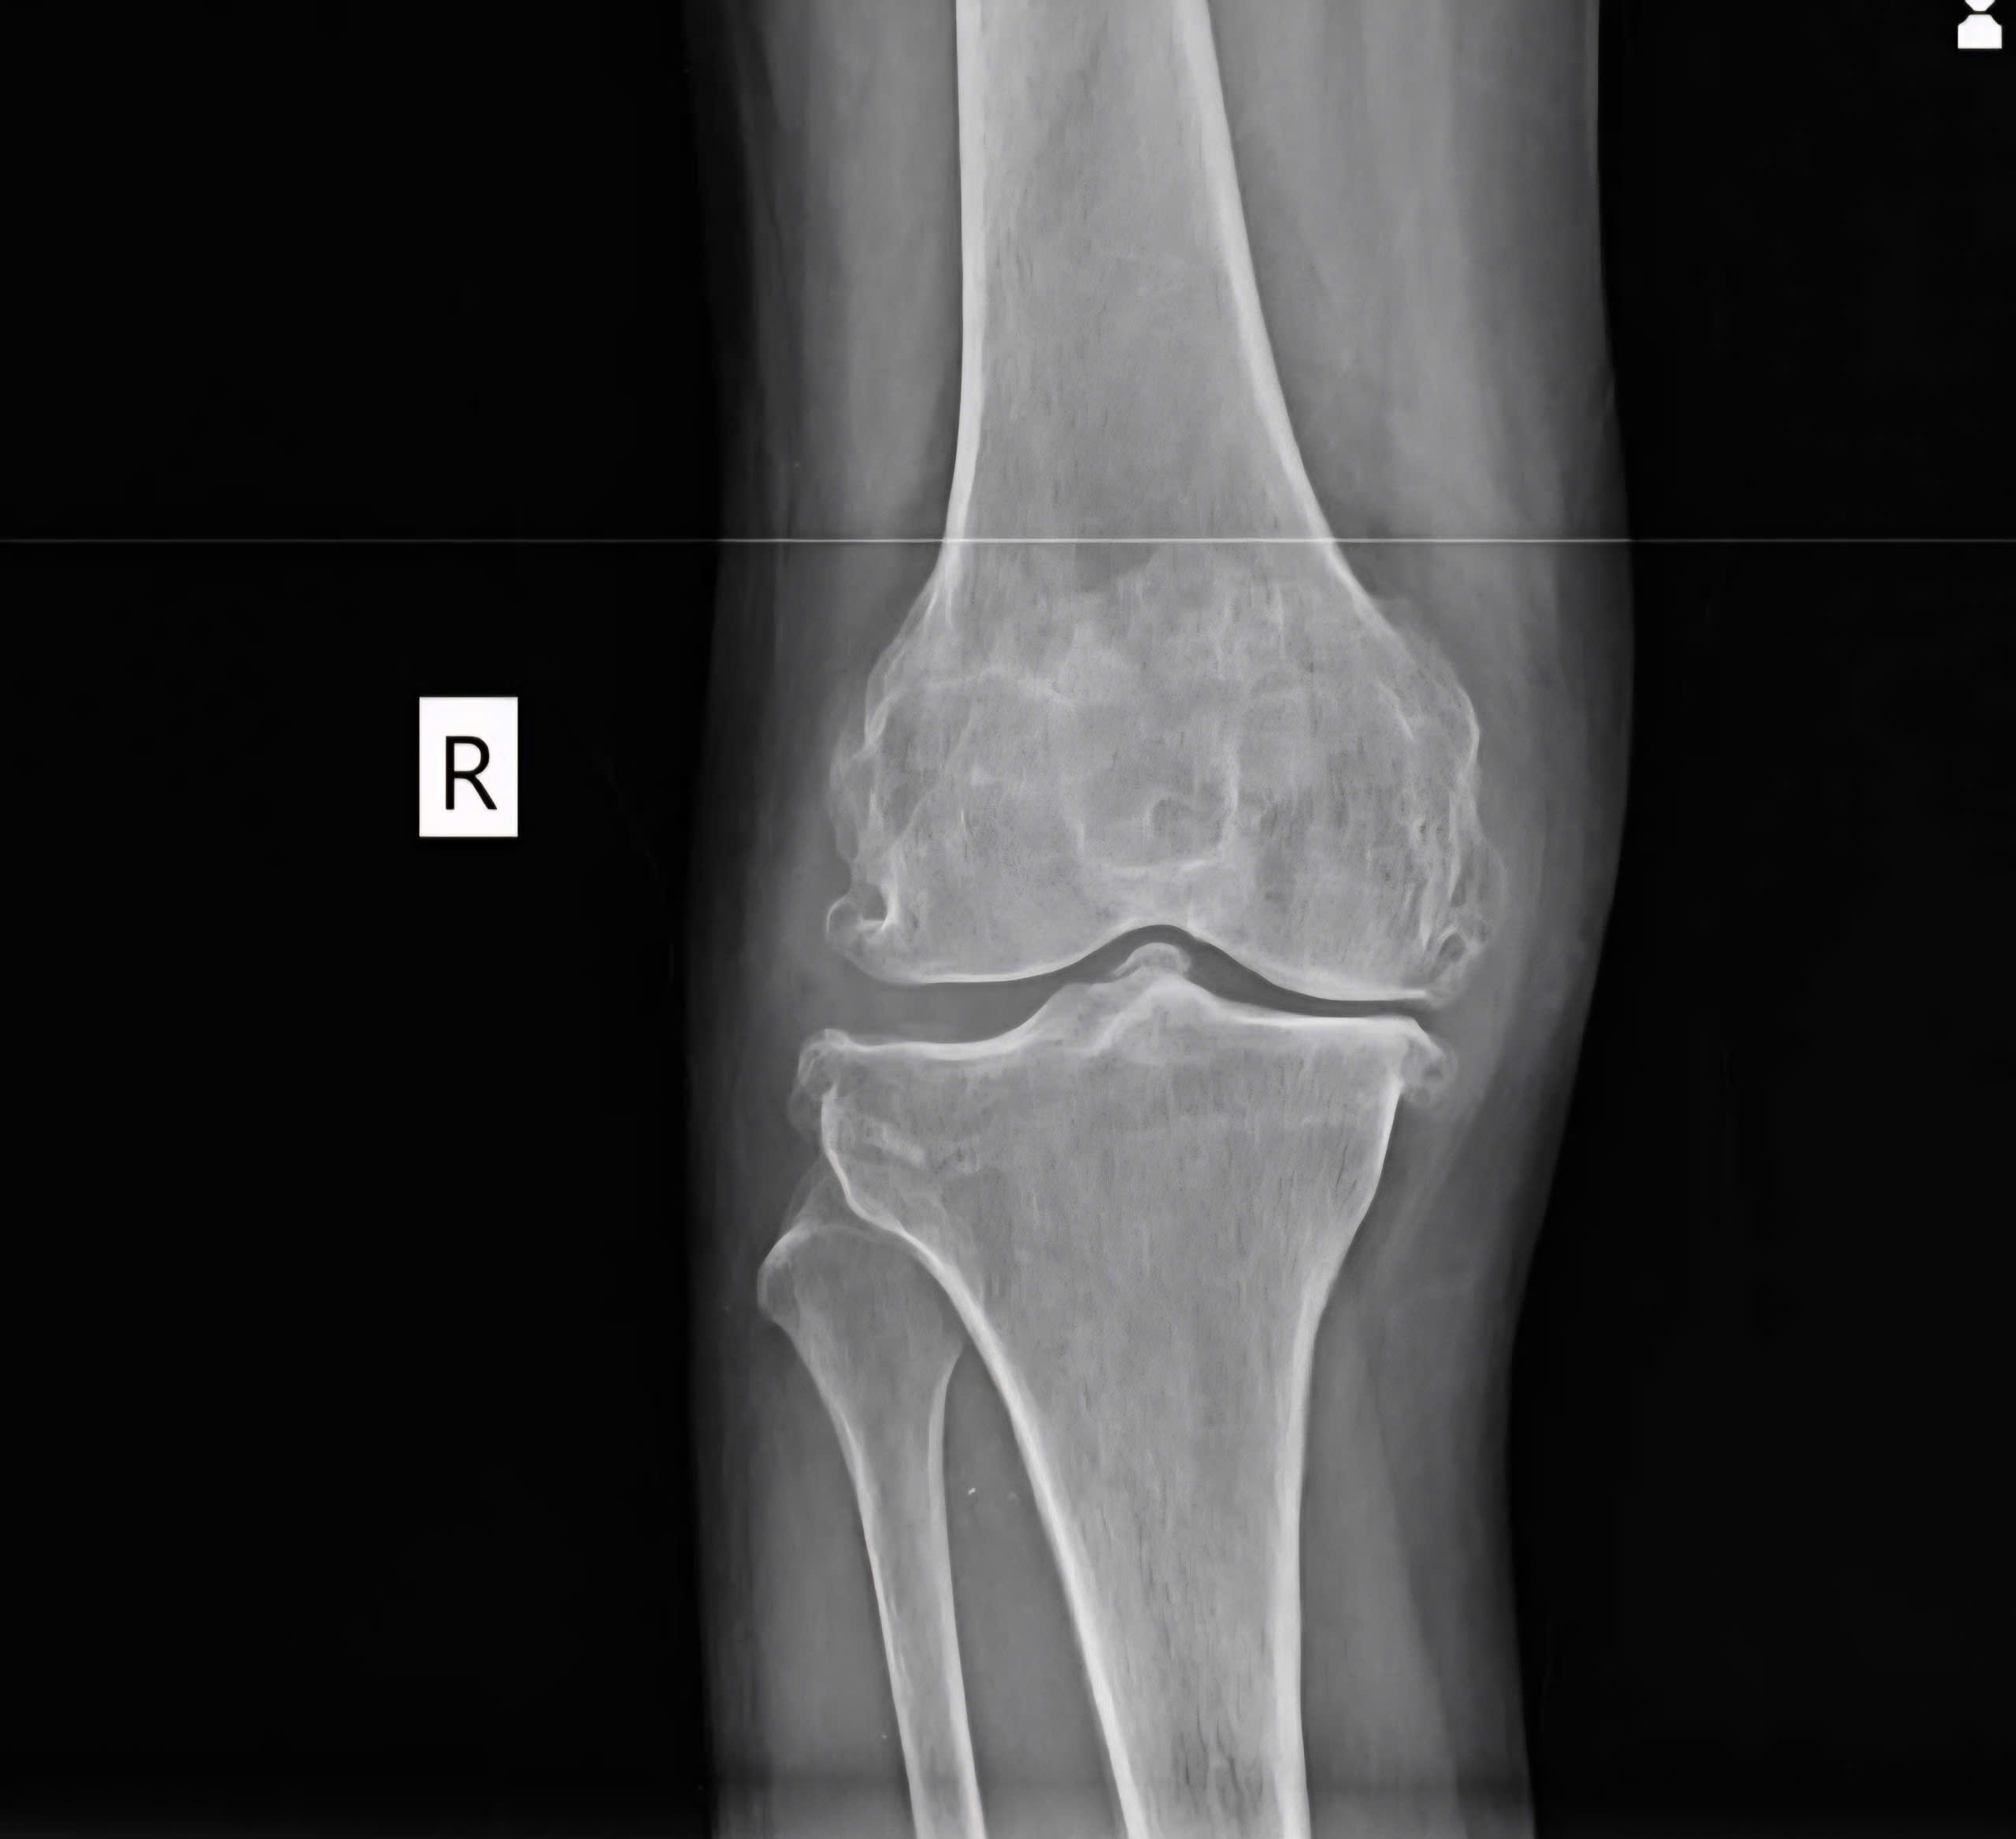

Khi bị thoái hóa khớp gối, lượng chất nhờn này giảm đi, khớp trở nên khô, đau, kêu lục cục.

Thoái hóa khớp gối nhẹ đến trung bình